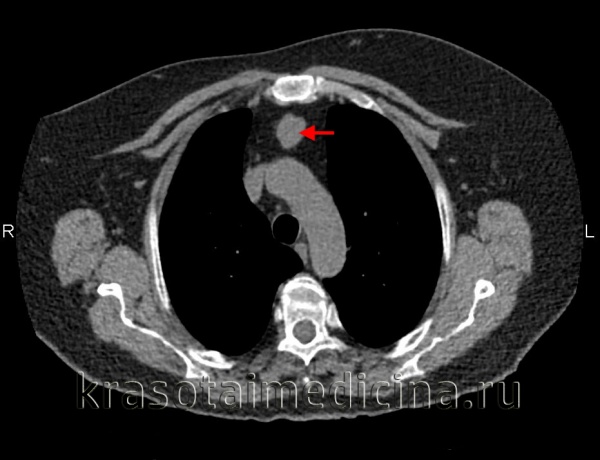

(а) У мужчины 27 лет при КТ с контрастным усилением в левой паравертебральной области определяется параганглиома, интенсивно накапливающая контрастное вещество. Параганглиомы являются гиперваскулярными опухолями, вблизи которых часто выявляются расширенные сосуды. Вследствие этого для планирования хирургического вмешательства или эмболизации может выполняться ангиография.

(б) У этого же пациента при МРТ на Т2ВИ визуализируется гиперинтенсивная зона в структуре объемного образования, что характерно для параганглиомы.